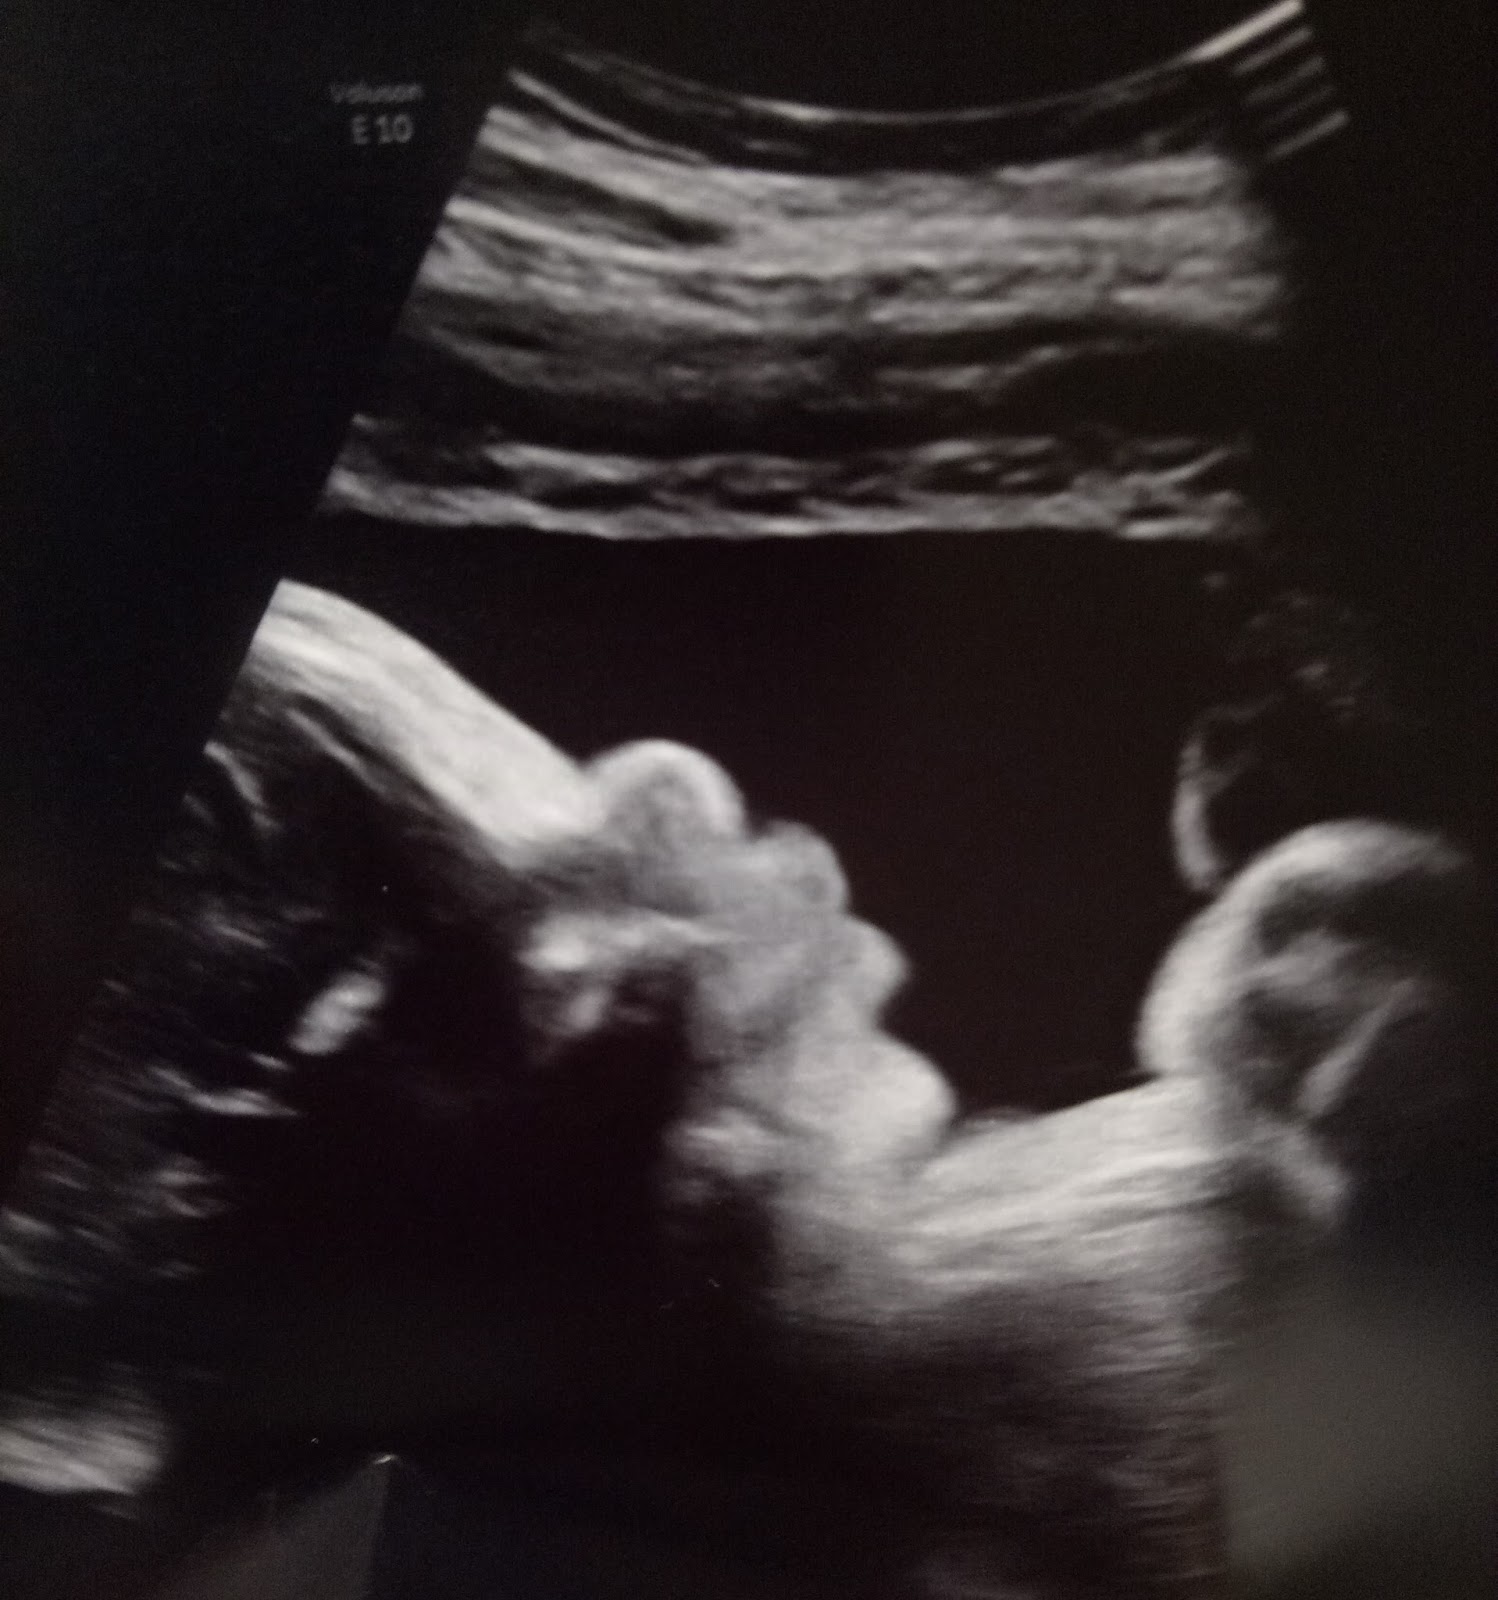

Yesterday we had a high risk ultrasound for baby. This was ordered due to some exposure to

various virus’ and diseases while in Papua, such as TB, Parvo, and others. The ultrasound looked good! Baby is growing,

and there was nothing alarming on the ultrasound. We got to see little peanut on 3D ultrasound,

and man does that girl have some cheeks!

She was pulling out all the stops for us, sticking her tongue out,

yawning, and practicing breathing. So

cute! Multiple times the doctor commented that she was a big baby. HA! Poor mom, but thank you Jesus for

everything looking healthy.